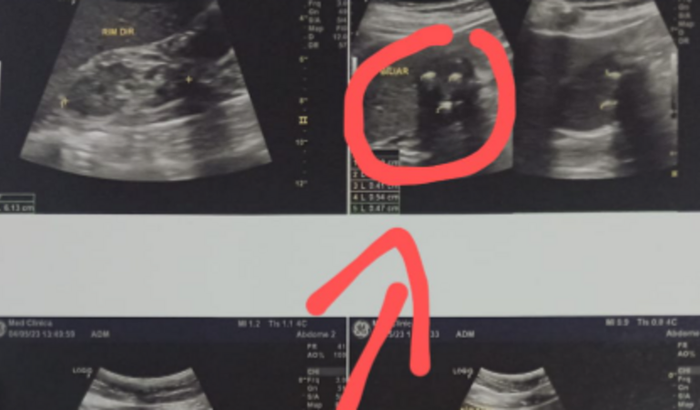

ME CHAMO CLEIDIMAR TENHO 56 ANOS ,DEPOIS DE VARIAS DORES DO ABDOME ,PAREI DE ME ALIMENTAR ,NÃO SENTIA MAIS FOME . APOS IR EM UMA CONSULTA MEDICA PARA VER QUE REALMENTE ESTAVA ACONTECENDO COMIGO ,O MEDICA ME PEDIU UM ULTRASSOM ABDOMINAL TOTAL,O QUAL CONSTATOY QUE ESTOU COM"LAMA BILIAR E MULTIPLOS CALCULOS NA BILIS ,OS QUAIS PRECISAM SER REMOVIDOS COM URGENCIA .SO QUE ESTA CIRUGIA SÓ TEM PARTICULAR E ESTOU PRECISANDO DA QUANTIA PARA FAZE LA JA QUE O MEDICO FALOU QUE É COM URGENCIA MINHA CIRUGIA.